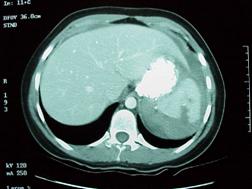

Leziune hepatica intraparenchimatoasa Leziune de lob drept

hepatic